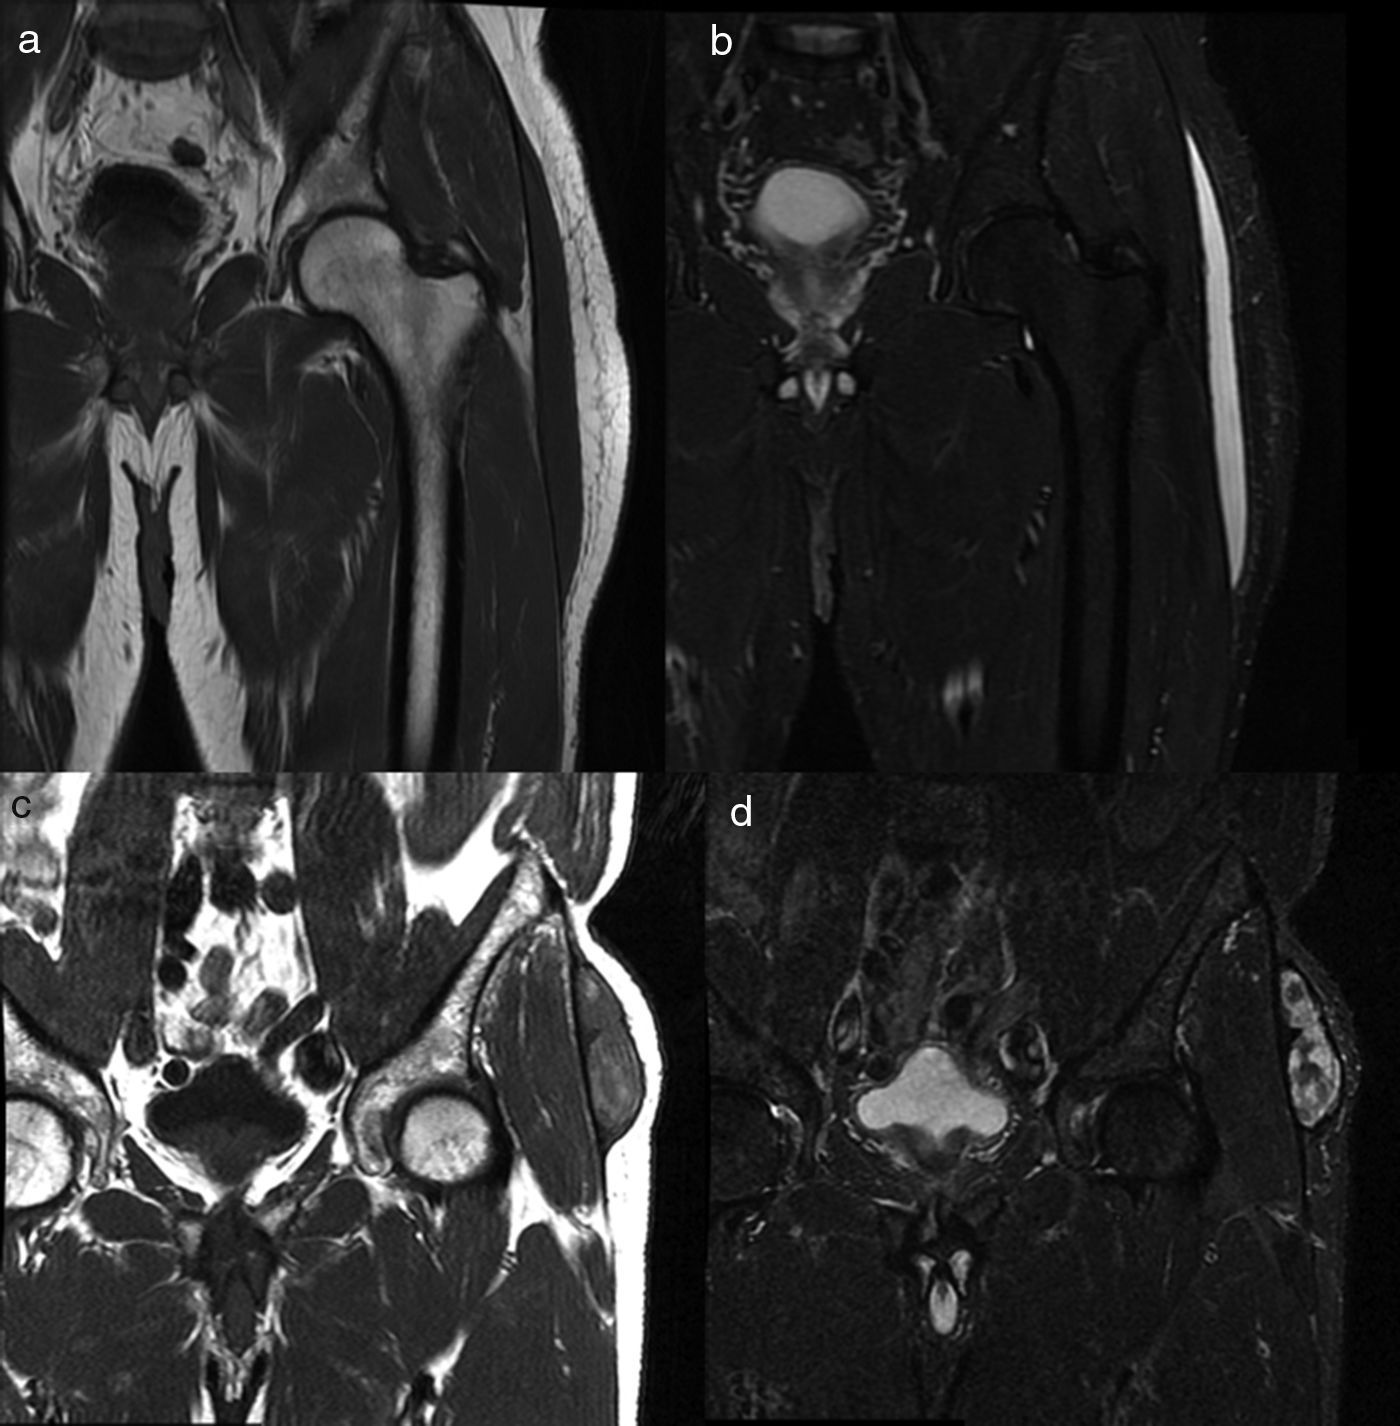

Material and methodsWe retrospectively reviewed 17 patients (11 men and 6 women; mean age, 56.1 years, range 25–81 years) diagnosed with Morel-Lavallée lesions in two different departments. All patients underwent ultrasonography, 5 underwent computed tomography, and 9 underwent magnetic resonance imaging. Percutaneous treatment with fine-needle aspiration and/or drainage with a 6–8F catheter was performed in 13 patients. Two patients required percutaneous sclerosis with doxycycline.

ResultsAll patients responded adequately to percutaneous treatment, although it was necessary to repeat the procedure in 4 patients.

ConclusionsRadiologists need to be familiar with this lesion that can be treated percutaneously in the ultrasonography suite when it is not associated with other entities.